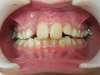

- Lorsque l’enfant serre les dents, on ne voit pas du tout les dents du bas ; il peut même exister des morsures palatines (l’enfant se mord !) car les incisives du bas touchent la gencive à chaque fois que l’enfant serre les dents. Il est donc impératif de commencer un traitement orthodontique très tôt afin de redonner une hauteur correcte à l’étage inférieur du visage de l’enfant, de le soulager d’éventuelles morsures au niveau du palais et de libérer la croissance de la mandibule vers l’avant. Dans ce cas, cette croissance de la mandibule vers l’avant est verrouillée et le décalage des maxillaires ne va faire que s’accentuer au fur et à mesure que l’enfant grandi ! un petit décalage peut s’aggraver de plus en plus si on laisse ce verrou de croissance !

- Lorsque l’enfant serre les dents du fond, celles de devant ne se recouvrent pas du tout : c’est ce qu’on appelle une béance ou infraclusion. Elle est souvent la résultante d’habitudes déformantes comme la succion du pouce ou de la tétine. L’élocution est altérée et il en résulte très fréquemment un chuintement, un «cheveu sur la langue » et une dysfonction linguale. La langue va tout le temps se positionner dans « le trou » et la déglutition ne va pas pouvoir devenir mature. La langue va constamment entretenir cette béance et tout l’environnement fonctionnel sera perturbé.

- Lorsque l’enfant serre les dents ; celles du haut passent derrière celles du bas : la croissance de la mâchoire supérieure ne peut pas se faire et ce décalage va s’aggraver au fur et à mesure que l’enfant grandit !

- Lorsque l’enfant a toujours la bouche ouverte du fait de la position des incisives maxillaires :

il existe un réel risque de fracture des dents qui ne sont à aucun moment protégées par les lèvres. Il est donc primordial pour l’enfant d’entreprendre un traitement orthodontique précoce afin de protéger ses dents qui sont définitives !